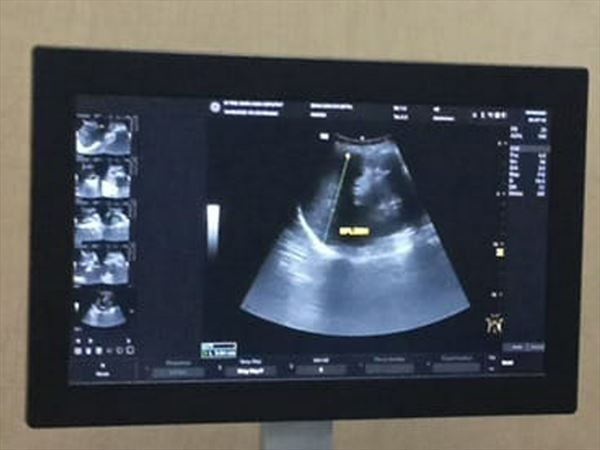

Badania USG są wykorzystywane w różnych obszarach medycyny, ponieważ pozwalają uzyskać dokładny obraz struktur wewnętrznych. Metoda ta nie wiąże się z bólem ani promieniowaniem rentgenowskim, co sprawia, że może być stosowana u szerokiej grupy pacjentów, w tym u kobiet w ciąży. Badania ultrasonograficzne odgrywają istotną rolę w wykrywaniu schorzeń na wczesnym etapie i umożliwiają monitorowanie postępu leczenia.

USG tarczycy z kolei pozwala na ocenę wielkości i struktury gruczołu, a także wykrywanie guzków lub innych nieprawidłowości. W przypadku problemów z układem mięśniowo-szkieletowym wykonywane są badania USG stawów, mięśni, ścięgien i więzadeł, umożliwiające lokalizację stanów zapalnych, uszkodzeń czy zmian pourazowych. Lekarz przeprowadza też USG piersi, płuc i węzłów chłonnych oraz specjalistyczne badania Dopplerowskie tętnic szyjnych oraz żył kończyn dolnych.

Zastosowanie ultrasonografii pozwala lekarzowi na szybkie i dokładne postawienie diagnozy, a pacjentom umożliwia uzyskanie informacji o stanie zdrowia w sposób bezpieczny i komfortowy.